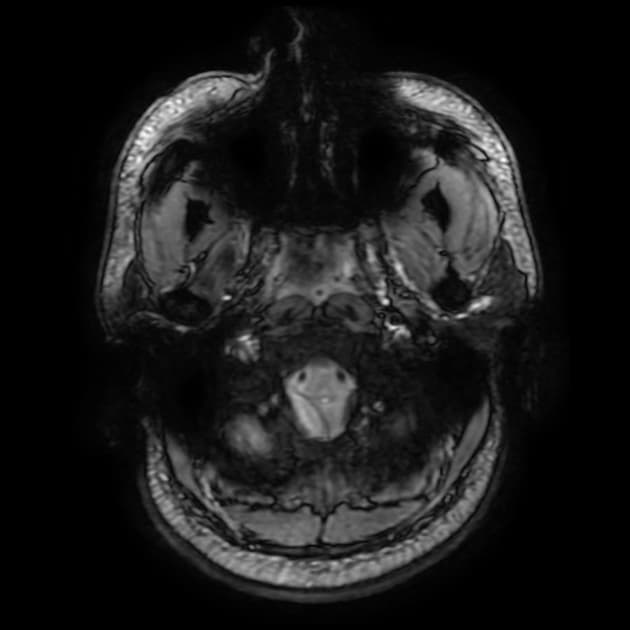

Axial T2

MRI•Axial T2•1 / 9

- Hoại tử xuất huyết (hemorrhagic necrosis) nhân bèo (putaminal) hai bên biểu hiện rõ qua tình trạng tăng tín hiệu (high signal) trên các chuỗi xung T1WI, T2WI và FLAIR.

- Ghi nhận có tín hiệu sụt giảm (drop out signal) trên chuỗi xung T2* GRE và hạn chế khuếch tán (diffusion restriction).

THẢO LUẬN (DISCUSSION): Việc pha trộn rượu giả là nguyên nhân phổ biến gây ngộ độc methanol (methanol intoxication) cấp tính (acute) ở các nước đang phát triển. Nhân bèo (putamina) là những vị trí dễ bị tổn thương nhất trong ngộ độc methanol; các dấu hiệu đặc trưng khác cần lưu ý bao gồm giảm tỷ trọng lan tỏa (diffuse hypo-attenuation) ở chất trắng đại não (cerebral white matter) và xuất huyết (hemorrhages).

- "Hoại tử nhân bèo hai bên là dấu hiệu hình ảnh kinh điển của ngộ độc methanol."

- "Chuyển dạng xuất huyết của các vùng hoại tử là phổ biến và được thấy dưới dạng sụt giảm tín hiệu trên T2* hoặc SWI."

- "Hạn chế khuếch tán ở nhân bèo xảy ra trong giai đoạn cấp tính do phù độc tế bào."

Ngộ độc methanol là một cấp cứu y khoa thường do uống phải rượu giả hoặc dung môi công nghiệp. Độc tính được trung gian bởi axit formic, một chất chuyển hóa của methanol, gây ức chế cytochrome c oxidase của ty thể, dẫn đến thiếu oxy tế bào. Nhân bèo đặc biệt nhạy cảm với sự tấn công chuyển hóa này, dẫn đến hoại tử hai bên và có thể kèm xuất huyết. Ngoài các hạch nền, độc tính methanol cũng có thể ảnh hưởng đến chất trắng dưới vỏ và dây thần kinh thị giác, trong đó tổn thương dây thần kinh thị giác thường dẫn đến suy giảm thị lực vĩnh viễn hoặc mù lòa.